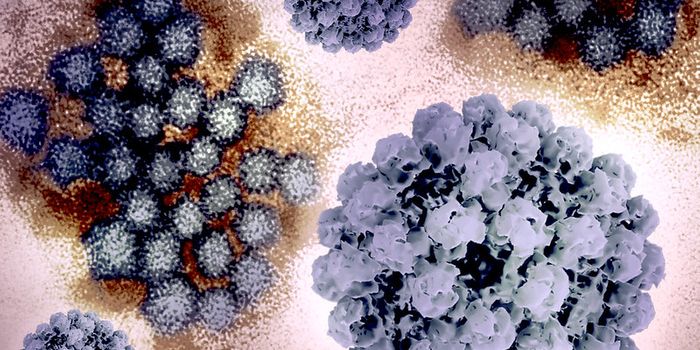

JAN 12, 2025MicrobiologyCases of norovirus have been surging around the United States in recent weeks. Norovirus is a very contagious pathogen t ...